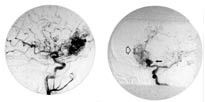

Neste dag ble det imidlertid i samråd med nevrokirurg utført cerebral angiografi, som, i tillegg til malformasjonen medialt frontalt høyre side (fig 2a), viste et stort aneurisme på a. communicans anterior (fig 2b). Hun ble overflyttet til nevrokirurgisk avdeling for endovaskulær behandling av dette store aneurismet. Fem dager senere ble hun tilbakeført til vår avdeling, og var da uten symptomer. Det er senere besluttet at behandling av malformasjonen fortsatt må ansees å være for risikabelt.